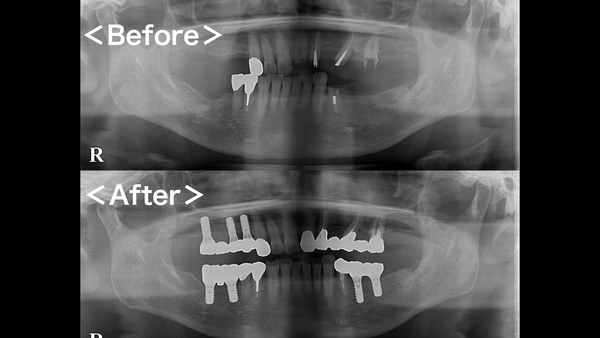

こちらが術前後のレントゲン写真になります。